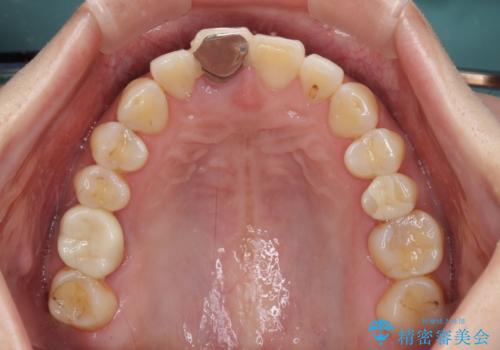

- 歯根が破折しているにもかかわらず、抜歯を避けてきたため痛みが発現したとのことで来院された患者様です。

歯根破折した歯は抜歯適用となるため、速やかに抜歯を行い、傷が治り次第オールセラミックブリッジにて補綴治療を行うこととしました。

抜歯による歯槽骨や歯肉が陥没して審美障害を起こすことがありますが、今回は仮歯でも違和感のない外観となったため、歯肉移植術を行うことなく仕上げることができました。